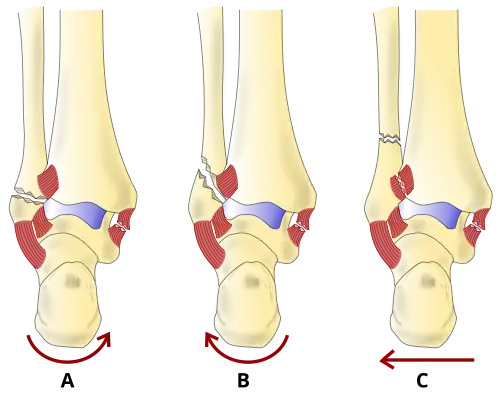

On X-rays, there can be a fracture of the medial malleolus, the lateral malleolus, and/or of the anterior/posterior margin of the distal tibia. The posterior margin (known as the posterior malleolus) is much more frequently injured than the anterior aspect of the distal tibia. If both the lateral and medial malleoli are broken, this is called a bimalleolar fracture (some of them are called Pott's fractures). If the posterior malleolus is also fractured, this is called a trimalleolar fracture.

There are several classification schemes for ankle fractures. Out of the following, the Lauge-Hansen and Danis-Weber classification systems are most commonly used.[9]

- The Lauge-Hansen classification categorizes fractures based on the mechanism of the injury as it relates to the position of the foot and the deforming force (the most common type is supination-external rotation)

- The Danis-Weber classification categorizes ankle fractures by the level of the fracture of the distal fibula (type A = below the syndesmotic ligament, type B = at its level, type C = above the ligament), with use in assessing injury to the syndesmosis and the interosseous membrane